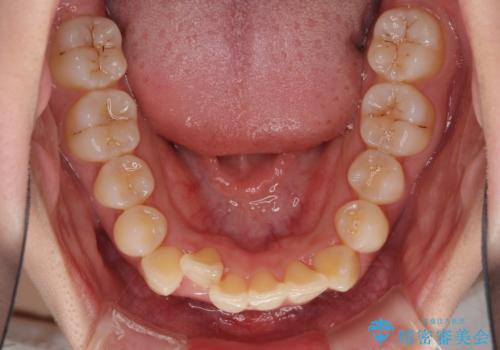

また、インプラント治療については、インビザラインによる矯正治療中の最適なタイミングで治療を行い、治療期間の短縮を図ることとしました。

インプラントは、治療期間を短くすることが可能な、ストローマン社のSLActiveを使用することとしました。

前歯のデコボコが強かったため、上の奥歯を後方に動かす量が多くなり、結果として2年以上の治療期間を擁することとなりました。

インプラント治療は当初の狙い通り、矯正治療期間中に行い、スムーズに処置を進めることができました。

歯並びが整ったことで治療前に認められた歯肉炎は全くなくなり、患者様には大変満足していただきました。